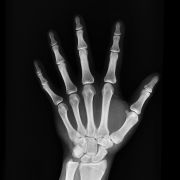

Röntgenuntersuchungen